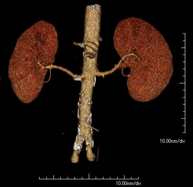

- Angio-TC aorta abdominal  Prueba diagnóstica no invasiva que consiste en el estudio de la arteria aorta abdominal obteniendo imágenes de alta definición anatómica mediante el empleo de un equipo de TC (Tomografía Computarizada) y de contraste yodado. La calidad de las imágenes permite realizar reconstrucciones en 2D y 3D gracias a estaciones de trabajo especializadas en el estudio arterial. Está indicado en aquellos pacientes con enfermedad vascular (aterosclerosis), en aneurismas de aorta, en pacientes con dolor abdominal de posible origen vascular, en estudios pre-quirúrgicos de lesiones adyacentes a la aorta abdominal como "mapa" vascular, etc. La información obtenida de forma no invasiva es indispensable para los pacientes que requieren tratamiento percutáneo o quirúrgico. En aquellos pacientes que solo requieren un seguimiento de las lesiones vasculares, esta técnica es la técnica no invasiva de elección junto con la angio-RM. Prueba diagnóstica no invasiva que consiste en el estudio de la arteria aorta abdominal obteniendo imágenes de alta definición anatómica mediante el empleo de un equipo de TC (Tomografía Computarizada) y de contraste yodado. La calidad de las imágenes permite realizar reconstrucciones en 2D y 3D gracias a estaciones de trabajo especializadas en el estudio arterial. Está indicado en aquellos pacientes con enfermedad vascular (aterosclerosis), en aneurismas de aorta, en pacientes con dolor abdominal de posible origen vascular, en estudios pre-quirúrgicos de lesiones adyacentes a la aorta abdominal como "mapa" vascular, etc. La información obtenida de forma no invasiva es indispensable para los pacientes que requieren tratamiento percutáneo o quirúrgico. En aquellos pacientes que solo requieren un seguimiento de las lesiones vasculares, esta técnica es la técnica no invasiva de elección junto con la angio-RM.

- Angio-TC arterias renales  Prueba diagnóstica no invasiva que consiste en el estudio de las arterias renales obteniendo imágenes de alta definición anatómica mediante el empleo de un equipo de TC (Tomografía Computarizada) y de contraste yodado. La calidad de las imágenes permite realizar reconstrucciones en 2D y 3D gracias a estaciones de trabajo especializadas en el estudio arterial. Esta prueba está indicada, por ejemplo, en aquellos pacientes que sufren de HTA refractaria al tratamiento, en pacientes con lesiones renales para tener un mapa "vascular" pre-quirúrgico, etc. Prueba diagnóstica no invasiva que consiste en el estudio de las arterias renales obteniendo imágenes de alta definición anatómica mediante el empleo de un equipo de TC (Tomografía Computarizada) y de contraste yodado. La calidad de las imágenes permite realizar reconstrucciones en 2D y 3D gracias a estaciones de trabajo especializadas en el estudio arterial. Esta prueba está indicada, por ejemplo, en aquellos pacientes que sufren de HTA refractaria al tratamiento, en pacientes con lesiones renales para tener un mapa "vascular" pre-quirúrgico, etc.